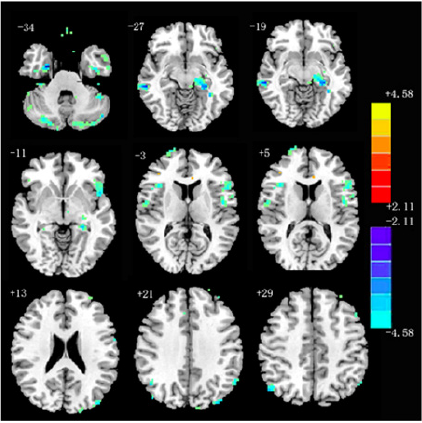

Alff values of bilateral cerebellar hemisphere, bilateral frontotemporal occipital parietal lobe, thalamus and basal ganglia in group A were significantly higher than those in group B (P < 0.05) (Figure 1). Alff values of right temporal lobe in group A1 were significantly higher than those in group A2 (P < 0.05). Alff values of bilateral cerebellar hemisphere, bilateral frontotemporal parietal lobe, left thalamus and basal ganglia in group A1 were significantly lower than those in group A2 (P < 0.05) (Figure 2).

Figure 2:

At present, the pathogenesis of migraine is not clear. At present, the mainstream theories of migraine pathogenesis mainly include trigeminal neurovascular theory and cortical spreading inhibition theory [6]. It is very important to explore the relationship between the changes of migraine brain functional areas and clinical manifestations, so as to achieve effective treatment results and improve the quality of life of migraine patients [7]. In this clinical study, the resting state fMRI technology was used to compare the brain functional activity areas of group A and group B. It was found that there were significant differences in Alff signal values of bilateral cerebellum, bilateral frontotemporal occipital parietal lobe, thalamus and basal ganglia in the case group (group A). The brain dysfunction areas in this study are similar to those in previous studies [8-10], and most of them are related to brain function areas about pain processing, such as frontal lobe, parietal lobe, temporal lobe, cerebellum, basal ganglia, etc. Studies have confirmed that there are lateral and medial pain systems in the brain, and the lateral pain system is responsible for pain recognition; The medial pain related system is responsible for processing the emotional and physical responses to pain. These two pain related systems can be combined into a pain related network, namely “pain matrix”. The pain matrix mainly includes frontal lobe, primary and secondary sensorimotor cortex, Anterior Cingulate Cortex (ACC), thalamus, Insular Cortex (IC), basal ganglia, cerebellum, amygdala, hippocampus, parietal lobe and temporal lobe [8,11]. Repeated migraine attacks can also lead to the reduction of cognitive function [4] and the damage of related brain functional areas, resulting in a vicious circle. This study found that compared with group B, migraine in group a can lead to cognitive dysfunction, specifically in visual space and executive, attention, orientation. In conclusion, according to whether there was patent forman ovale, this study divided migraine patients into different groups, and revealed the abnormal changes of brain functional areas in migraine patients more intuitively by resting state fMRI. At the same time, through the comparison of MOCA score, it revealed that migraine can lead to cognitive dysfunction in patients, manifested in visual space and executive, attention and orientation. Therefore, this study is helpful to explore the pathogenesis of migraine and guide the treatment according to the clinical manifestations.